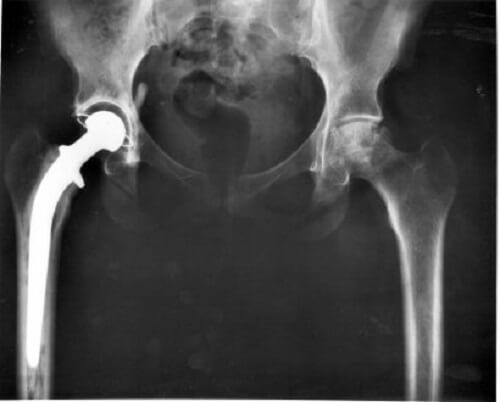

Bir köpeğin arka bacakları güçsüzleşmeye başladığında – ya da felç olduğunda dahi – bunun üç ana nedeni vardır: Nörolojik, ortopedik ya da semptomatik. Sebepler nörolojik olduğunda, paraparezi ya da akut parapleji denilen bir şey ortaya çıkar.

Bu tür felçlerin (arka ayaklardaki güçsüzlük ile başlar) en sık karşılaşılan nedeni, köpeklerde çok yaygın olan ve kedilerde çok nadir görülen dejeneratif bir vertebral disk hastalığı olma eğilimidir.

Bu durum Hansen I tipi bel fıtığı olarak bilinir. Daha kronik bir ilerleme sürecine sahip olan ve bu sebeple daha az agresif olan Hansen II tipi bel fıtığı da var.

Hansen I bel fıtığı diğer köpek cinslerinin yanı sıra, özellikle Dukhund (Porsuk köpeği), Cocker Spaniel, Beagle, Pekingese (Pekinez) ve Shih Tzu’lara zarar verir. Köpeğinizin sırtında fıtık olduğunu düşünüyorsanız ya da bir veteriner köpeğinize bu tanıyı koyduysa, bir nöroloji uzmanını ziyaret etmekte tereddüt etmeyin.

Köpeğiniz tedavi edilmemiş bir bel fıtığı ile ne kadar uzun süre devam ederse, hastalığın neticesi de o kadar kötü olabilir. Ancak hayvanınızdaki fıtığı zamanında fark ederseniz, bu problemin ameliyatla giderilmesini sağlayabilirsiniz.